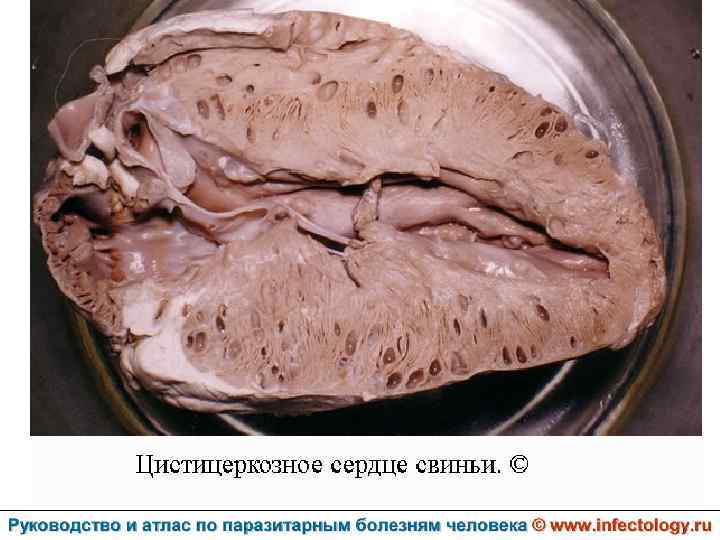

Цистицеркоз (шифр по МКБ 10 - B 69) – биогельминтоз, который вызывается паразитированием в тканях и органах человека и животных личиночной стадии цепня вооруженного – цистицерка (Cysticercus cellulosae) Болезнь проявляется разнообразными симптомами в зависимости от локализации цистицерков.